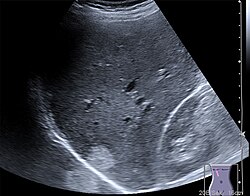

Die Sonde sendet kurze, gerichtete Schallwellenimpulse aus, die an Gewebe-Grenzschichten und in inhomogenen Geweben unterschiedlich stark reflektiert und gestreut werden, was als Echogenität bezeichnet wird. Aus der Laufzeit der reflektierten Signale kann die Tiefe der reflektierenden Struktur ermittelt werden. Die Stärke der Reflexion wird vom Ultraschallgerät als Grauwert auf einem Monitor dargestellt. Strukturen geringer Echogenität werden dunkel bzw. schwarz, Strukturen hoher Echogenität werden hell oder weiß dargestellt. Gering echogen sind vor allem Flüssigkeiten wie Harnblaseninhalt und Blut. Eine hohe Echogenität besitzen Knochen, Gase und sonstige stark schallreflektierende Material-Grenzflächen. Die Echogenität innerhalb eines Organs oder eines Krankheitsherdes wird als Binnenecho bezeichnet.

Von den Monitorbildern werden zur Dokumentation Ausdrucke, sogenannte Sonogramme, oder gelegentlich Videoaufnahmen gemacht. Schwangeren wird häufig auch ein Bild ihres ungeborenen Kindes überlassen.